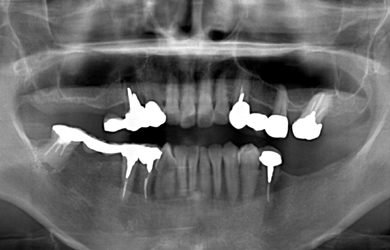

治療前

• 治療前

治療方針 右上の骨がほとんど無いため、サイナスリフト法に再生療法を組み合わせ上顎洞底部を挙上することにより、骨の無い部分に骨をつくってあげ、インプラント治療を可能にする。

治療内容 インプラント5本(抜歯即日スピードインプラント+サイナスリフト+GBR+クラウンレングスニング)、ハイブリッドセラミック8本

治療部位

6 5 4 3

7 6 5 4